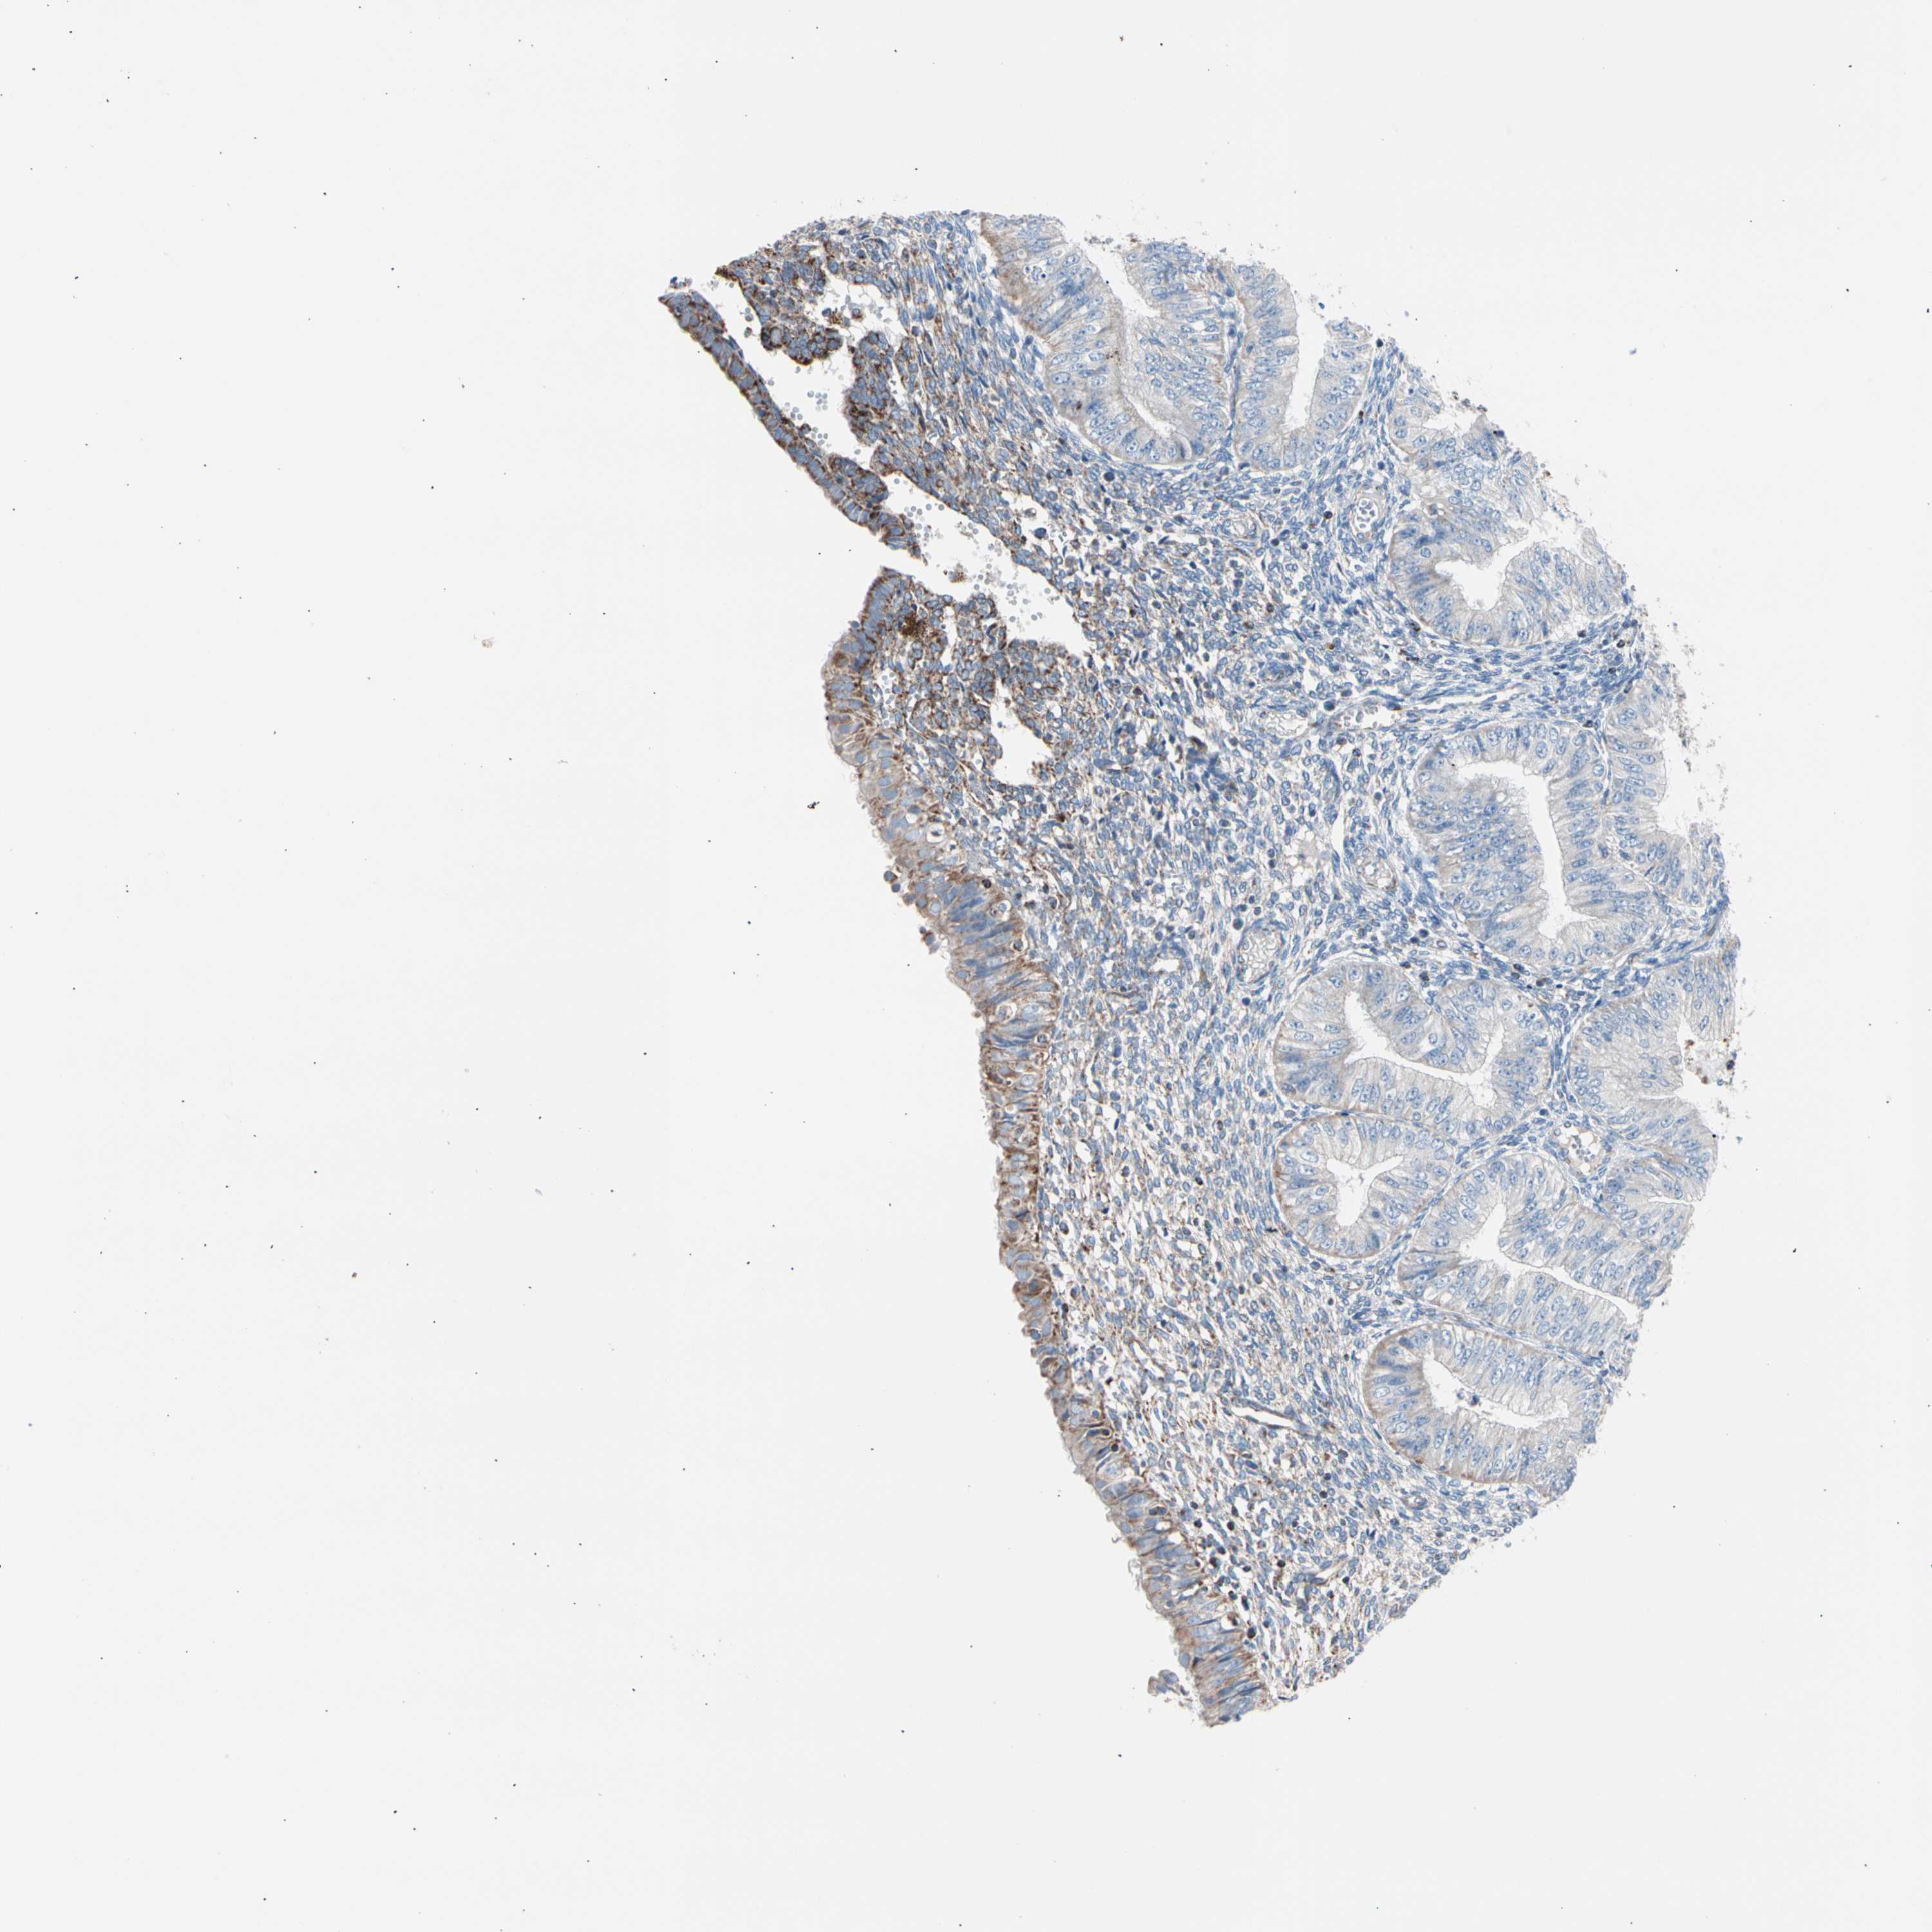

ENDOMETRIAL CANCER - Protein expressioni

A mouse-over function shows sample information and annotation data. Click on an image to view it in a full screen mode. Samples can be filtered based on level of antibody staining by selecting one or several of the following categories: high, medium, low and not detected. The assay and annotation is described here.

Note that samples used for immunohistochemistry by the Human Protein Atlas do not correspond to samples in the TCGA dataset.

Antibody stainingi

Antibody staining in the annotated cell types in the current human tissue is reported as not detected, low, medium, or high, based on conventional immunohistochemistry profiling in selected tissues. This score is based on the combination of the staining intensity and fraction of stained cells.

Each image is clickable and will lead to virtual microscopy that enables deeper exploration of all samples and also displays staining intensity scores, fraction scores and subcellular localization as well as patient and tissue information for each sample.

Antibody HPA007043

Antibody HPA007044

Antibody CAB010052

Staining

High

Medium

Low

Not detected

Intensity

Strong

Moderate

Weak

Negative

Quantity

>75%

75%-25%

<25%

None

Location

Nuclear

Cytoplasmic/membranous

Cytoplasmic/membranous,nuclear

Adenocarcinoma, NOS